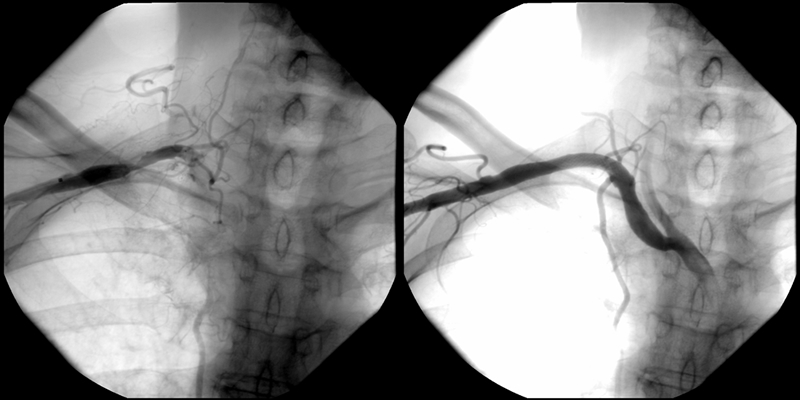

- 3枝閉塞 【写真】

- 脛骨腓骨動脈幹(peroneal trunk) 【写真】

- 後脛骨動脈(posterior tibial artery) 【写真】

考え方としては、早期であるほど2の血管内手術のみで治る可能性が高いと考えてよいでしょう。現在の末梢動脈に対する血管内手術の適応は、大動脈・腸骨動脈領域から膝下動脈、さらに足関節から足趾にまで及びます。しかし、それぞれの治療法には当然ながら適応があります。このためしばしば従来からの手術との組み合わせであるハイブリッド手術が必要になりますが、血管内呪術の関与する割合は8~9割にも及んでいます。